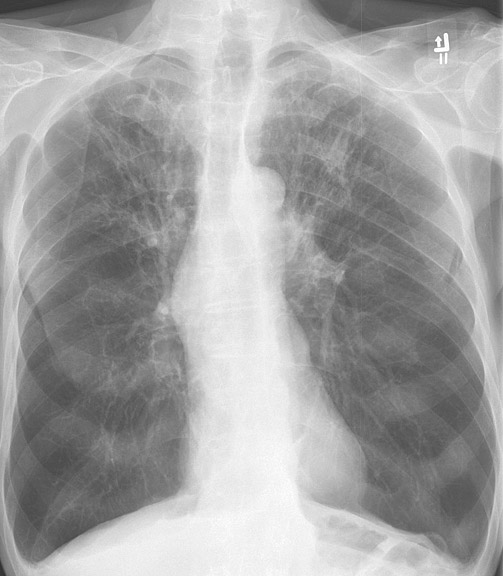

COPD